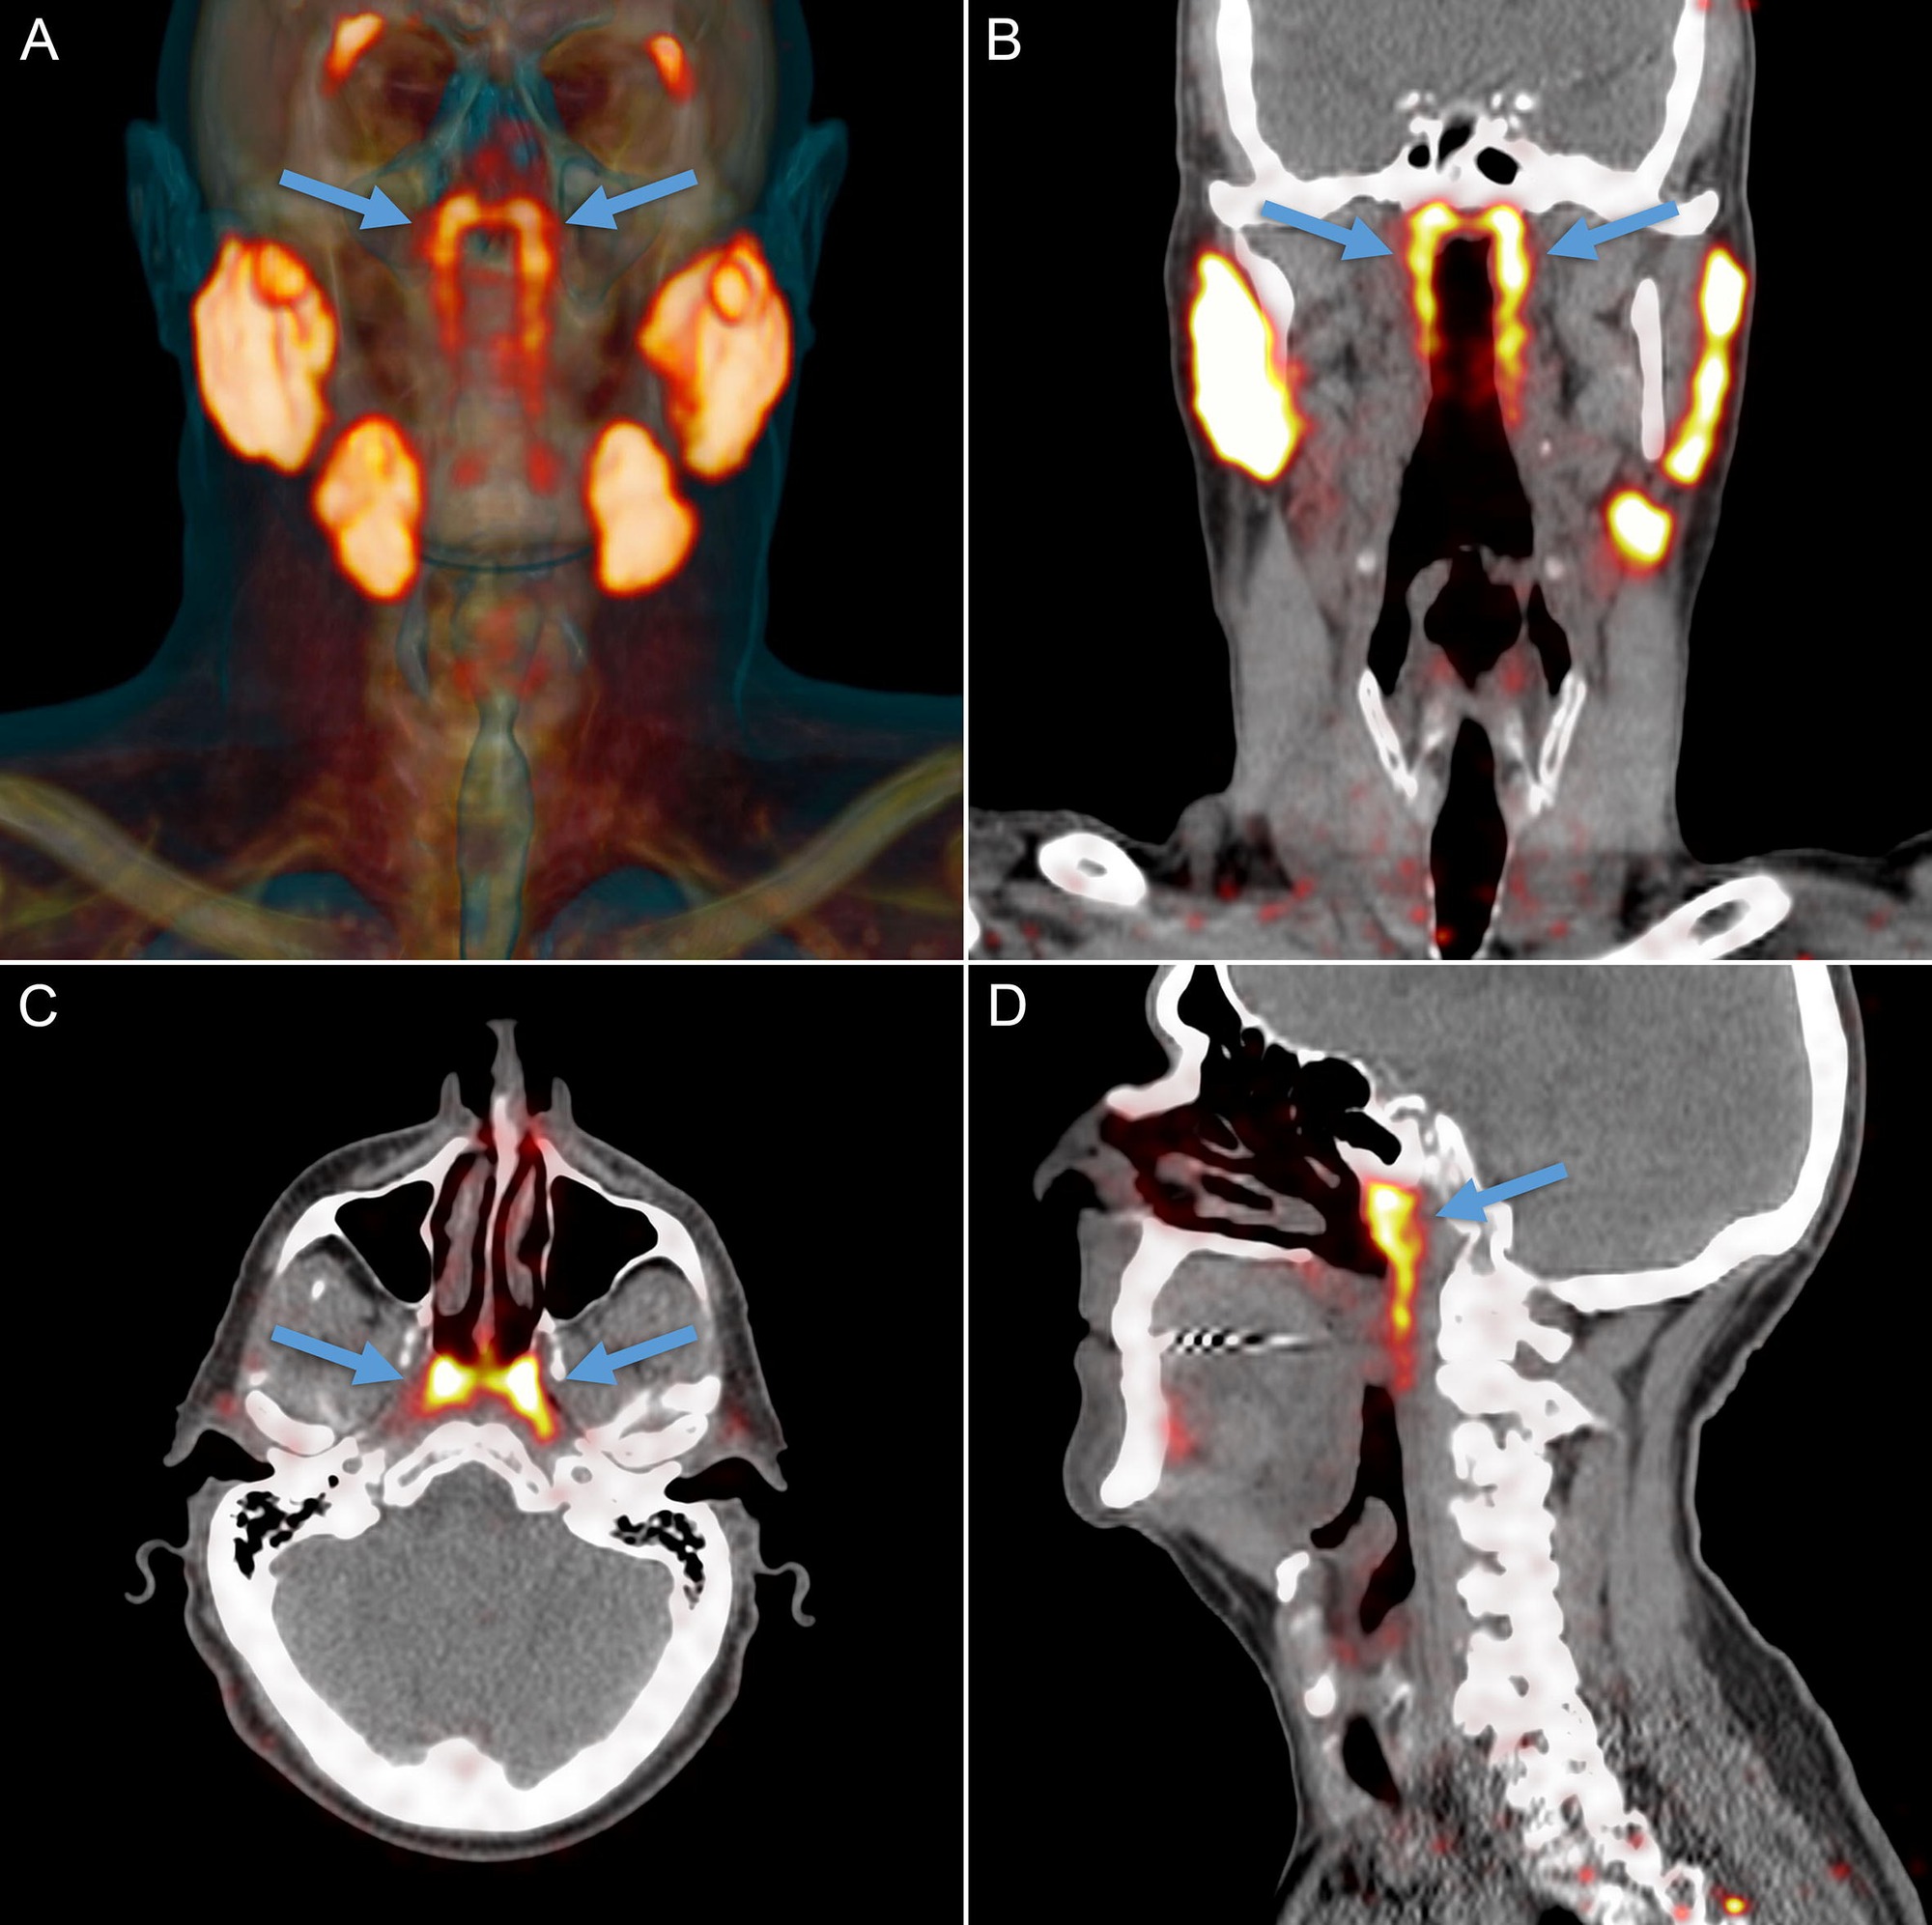

Theo PubMed, vào năm 2020, các nhà nghiên cứu Hà Lan công bố phát hiện một cặp tuyến nước bọt mới nằm ngay phía sau mũi, trong khu vực nối giữa khoang mũi và họng. Sau đó, nó đã được các chuyên gia đặt tên là tuyến nước bọt ống hầu (tubarial salivary glands). Phát hiện này lập tức làm dậy sóng truyền thông và cộng đồng khoa học vì nếu đúng, nó sẽ bổ sung vào "bản đồ" giải phẫu người vốn tự hào có 3 cặp tuyến nước bọt lớn đã được biết đến lâu nay.

Theo NKI, câu chuyện bắt đầu không phải từ phòng mổ giải phẫu mà từ… máy PET/CT cho bệnh nhân ung thư tiền liệt tuyến. Khi các bác sĩ tiêm chất đánh dấu và soi hình ảnh, họ thấy hai vùng sáng bất thường ở vòm họng xuất hiện nhất quán trong hàng loạt bệnh nhân đã gợi ý có một cấu trúc tuyến lớn hơn những "tuyến nhỏ rải rác" mà sách y đã mô tả trước đó. Khám nghiệm thêm trên xác và phân tích mô cho thấy tồn tại mô tuyến với nhiều ống dẫn, đủ để các tác giả đặt vấn đề đây là một "vùng tuyến" có thể coi là cơ quan.